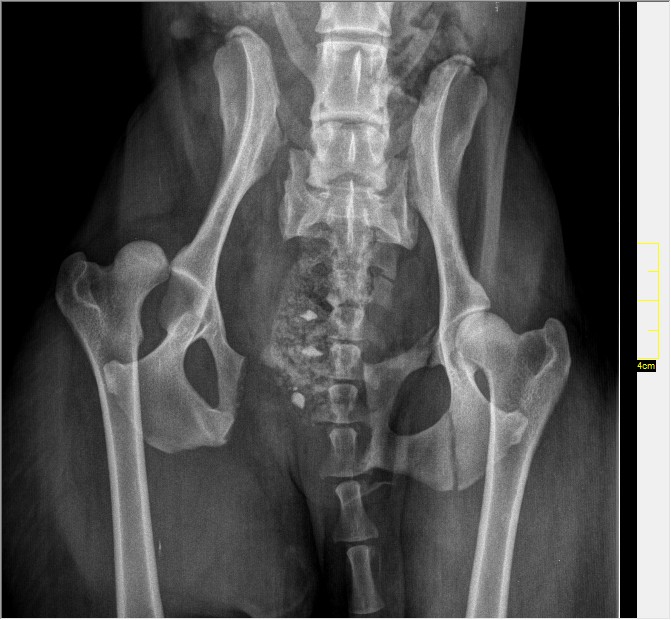

Mirka a été accidentée, fracture du bassin. Nous avons besoin de parrains pour financer son opération, ses radios et soins. merci de cliquer sur je parraine

MIRKA, écrasée par un tracteur, est arrivée complètement paralysée, souffrant le martyr chez le vétérinaire. Le propriétaire n'a pas souhaité la garder ni payer les frais vétérinaires. Elle est donc confiée aux bons soins de la spa sud alpine, nous n'avons pas pu nous résoudre, bien sûr à endormir cette gentille chienne de 3 ans. Mirka a été opérée et se remet tout doucement de son accident. Les frais sont toutefois très élevés et nous comptons sur la générosité des parrains.